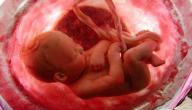

مع بداية الأسبوع الثالث والعشرين يبدأ وزن الجنين وطوله بالزيادة ليقارب حجمه حجم فاكهة المانجو الكبيرة، أو الجريب فروت، ويبدأ الجنين بالتحرُّك والرقص خصوصاً عند استلقاء الأم على ظهرها، وعلى الرغم من تطوُّر الرئتَين إلّا أنَّ الجنين لا يستيطع الاعتماد عليهما لإتمام عمليّة التنفُّس، ولكنَّه يُؤدِّي بعض حركات التنفُّس في هذه المرحلة، ومن ناحية أخرى يبدأ الشعر الناعم الذي يُغطِّي جسم الجنين باتِّخاذ لون أغمق، ومن الممكن رؤيته، وتمييزه بصورة الموجات فوق الصوتيّة.[٣]

يتميَّز الأسبوع الرابع والعشرون بنُموِّ عضلات الوجه، ممَّا يجعل الجنين مشغولاً بصناعة تعابير الوجه المختلفة، وتجربة عضلات وجهه، ورفع حواجبه وخفضها، وتجدر الإشارة إلى أنَّ الأطبَّاء يُشيرون إلى إمكانيّة نُموِّ الجنين، وتطوُّره في حال ولادته في هذا الأسبوع، فقد اكتملت الرئتان، وأصبحتا قادرتَين على أداء وظائفهما بشكل جيِّد، إلّا أنَّ هذا يتطلَّب رعاية صحِّية مُتخصِّصة.[٤]